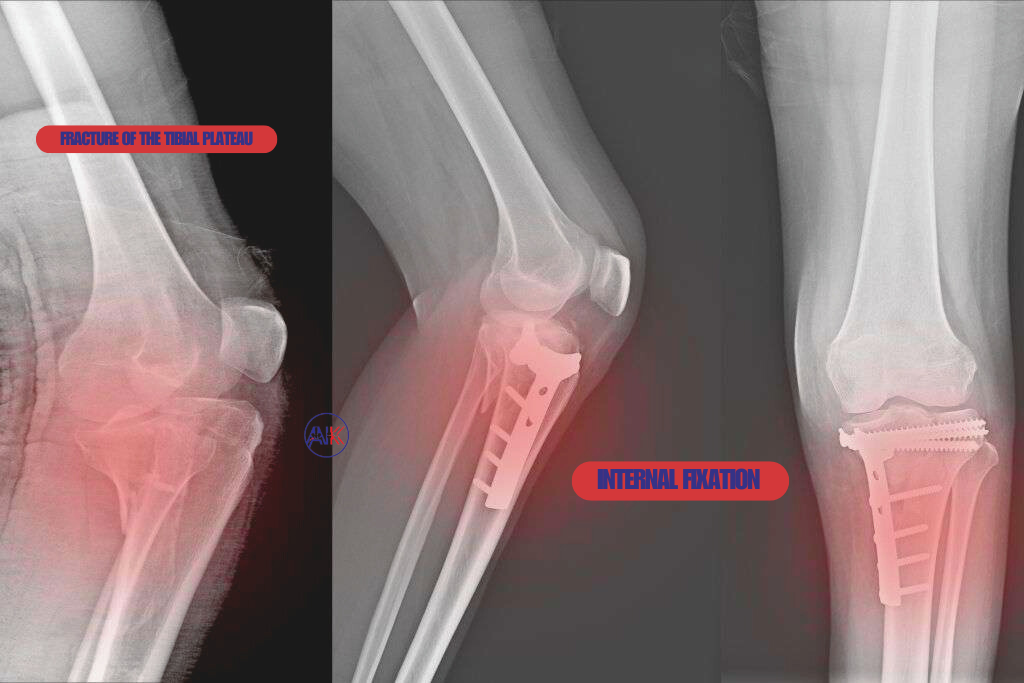

Tibial Plateau Fractures: Fractures involving the top surface of the tibia (shinbone) that meet the knee joint, often from falls or car accidents.

For complex fractures or injuries that involve multiple bone fragments, surgical intervention may be necessary to achieve proper alignment and stabilisation. Dr Keeley is highly experienced in performing advanced surgical procedures using the latest techniques and technologies, all aimed at ensuring the best possible outcomes for his patients.

This technique uses metal plates, screws, or rods to stabilise bone fragments during healing. It’s often necessary for fractures that cannot be managed with immobilisation alone.

Surgical Treatment: If surgery is required, Dr Keeley will perform the procedure using the latest techniques, such as internal fixation with screws or plates, to ensure proper alignment and stabilisation of the injury. In cases where non-surgical treatment is appropriate, immobilisation (e.g., casting or bracing) and pain management will be initiated.